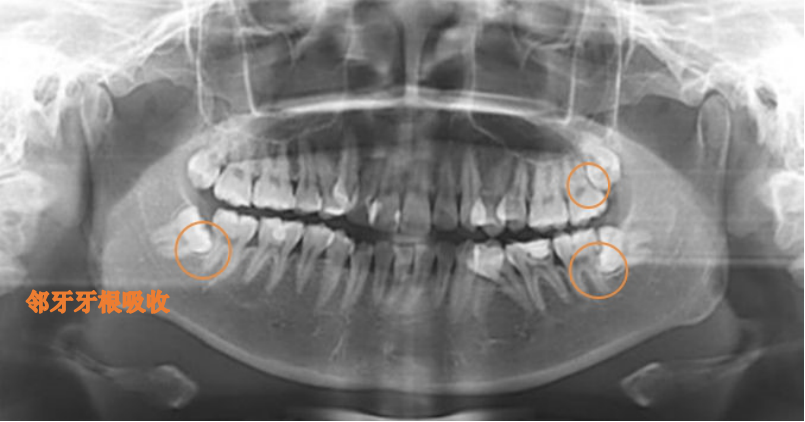

拔:当智齿位置不正挤压导致前方第二磨牙龋坏或者牙齿松动,一般建议先行拔除智齿后酌情治疗第二磨牙。

医生我的智齿离神经很近,拔牙会损伤神经嘛,如果神经损伤会面瘫嘛,有没有什么影响?

拔牙时下牙槽神经损伤主要是因为个别牙齿与神经关系密切,拔牙操作中牙和骨的相对运动会导致神经受压、牵拉、术后水肿等而受损。而下牙槽神经症状的风险,在不同牙齿的拔除中是不同的,牙根或整个牙齿与神经关系越紧密,这种风险就越大。根据国内外研究,在智齿拔除术中,下牙槽神经受影响的几率是1~3%。其中大部分病人会在3~6个月内恢复感觉。

1. 20岁以后牙根已逐渐形成,会压迫下牙槽神经,损伤下牙槽神经几率大;

2. 20以后智齿牙根发育完成,拔牙阻力增加,拔出相对困难,术后疼痛肿胀会相应加剧;

3. 20岁以后发育完成的牙根可能存在变异,多根,弯根,这就增加了拔牙难度;